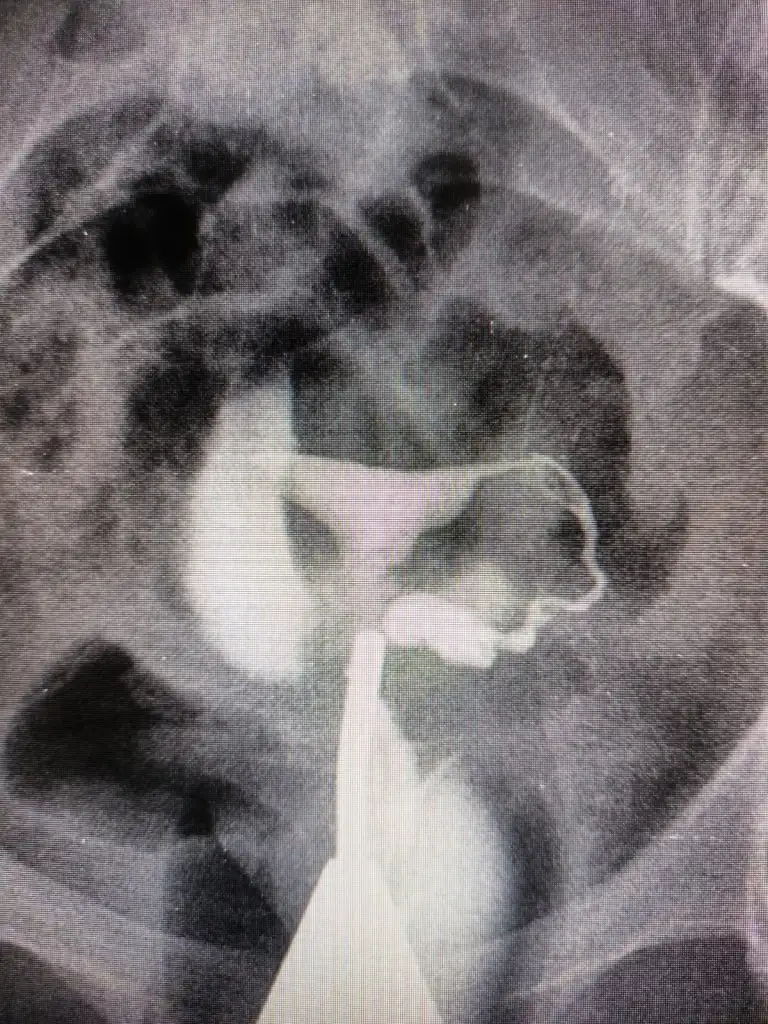

Valla bilemedim hidrosalpenks tıkanıp da içinde sıvı birikmesi. E hidrosalpenks demişlerse az da olsa bir tıkanıklık ve sıvı var demekki ve kendi icindeki sıvı yüzünden o tüpte gebelik oluşmayabiliyor eğer rahime geri sıvı akışı yapmıyorsa diğer tüple gebelik oluşur sıkıntı olmaz bence tabi doktorunuz sizin durumunuzu daha iyi bilir ben bu konu yüzünden her gördüğüm jinekologla konuştum resmen 1 aydır geceli gündüzlü bunu araştırıyorumKalınlık yazılmamış " tubalarda geçiş izlendi sol tüp hidrosalpinks? " Şeklinde yazılmış